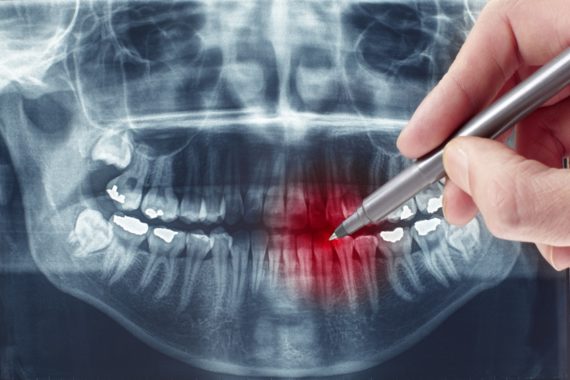

Die Anfertigung von Röntgenbildern ist in der Zahnmedizin eine der wichtigsten Voraussetzungen für die Erstellung von Diagnosen und Behandlungsplänen. Digitales Röntgen verzichtet auf Filme und Fotochemikalien. Stattdessen werden mittels eines Sensors, der den Röntgenfilm ersetzt, die Bilder direkt auf einen Computer weitergeleitet. Dieser Vorgang benötigt nur wenige Sekunden. Der behandelte Zahnarzt kann diese Bilder direkt vergrößern, Ausschnitte auswählen, Kontrast und Helligkeit verändern sowie auf viele verschiedene Weisen das Bild verändern. Dadurch lässt sich eine absolut präzise Diagnose erzielen.